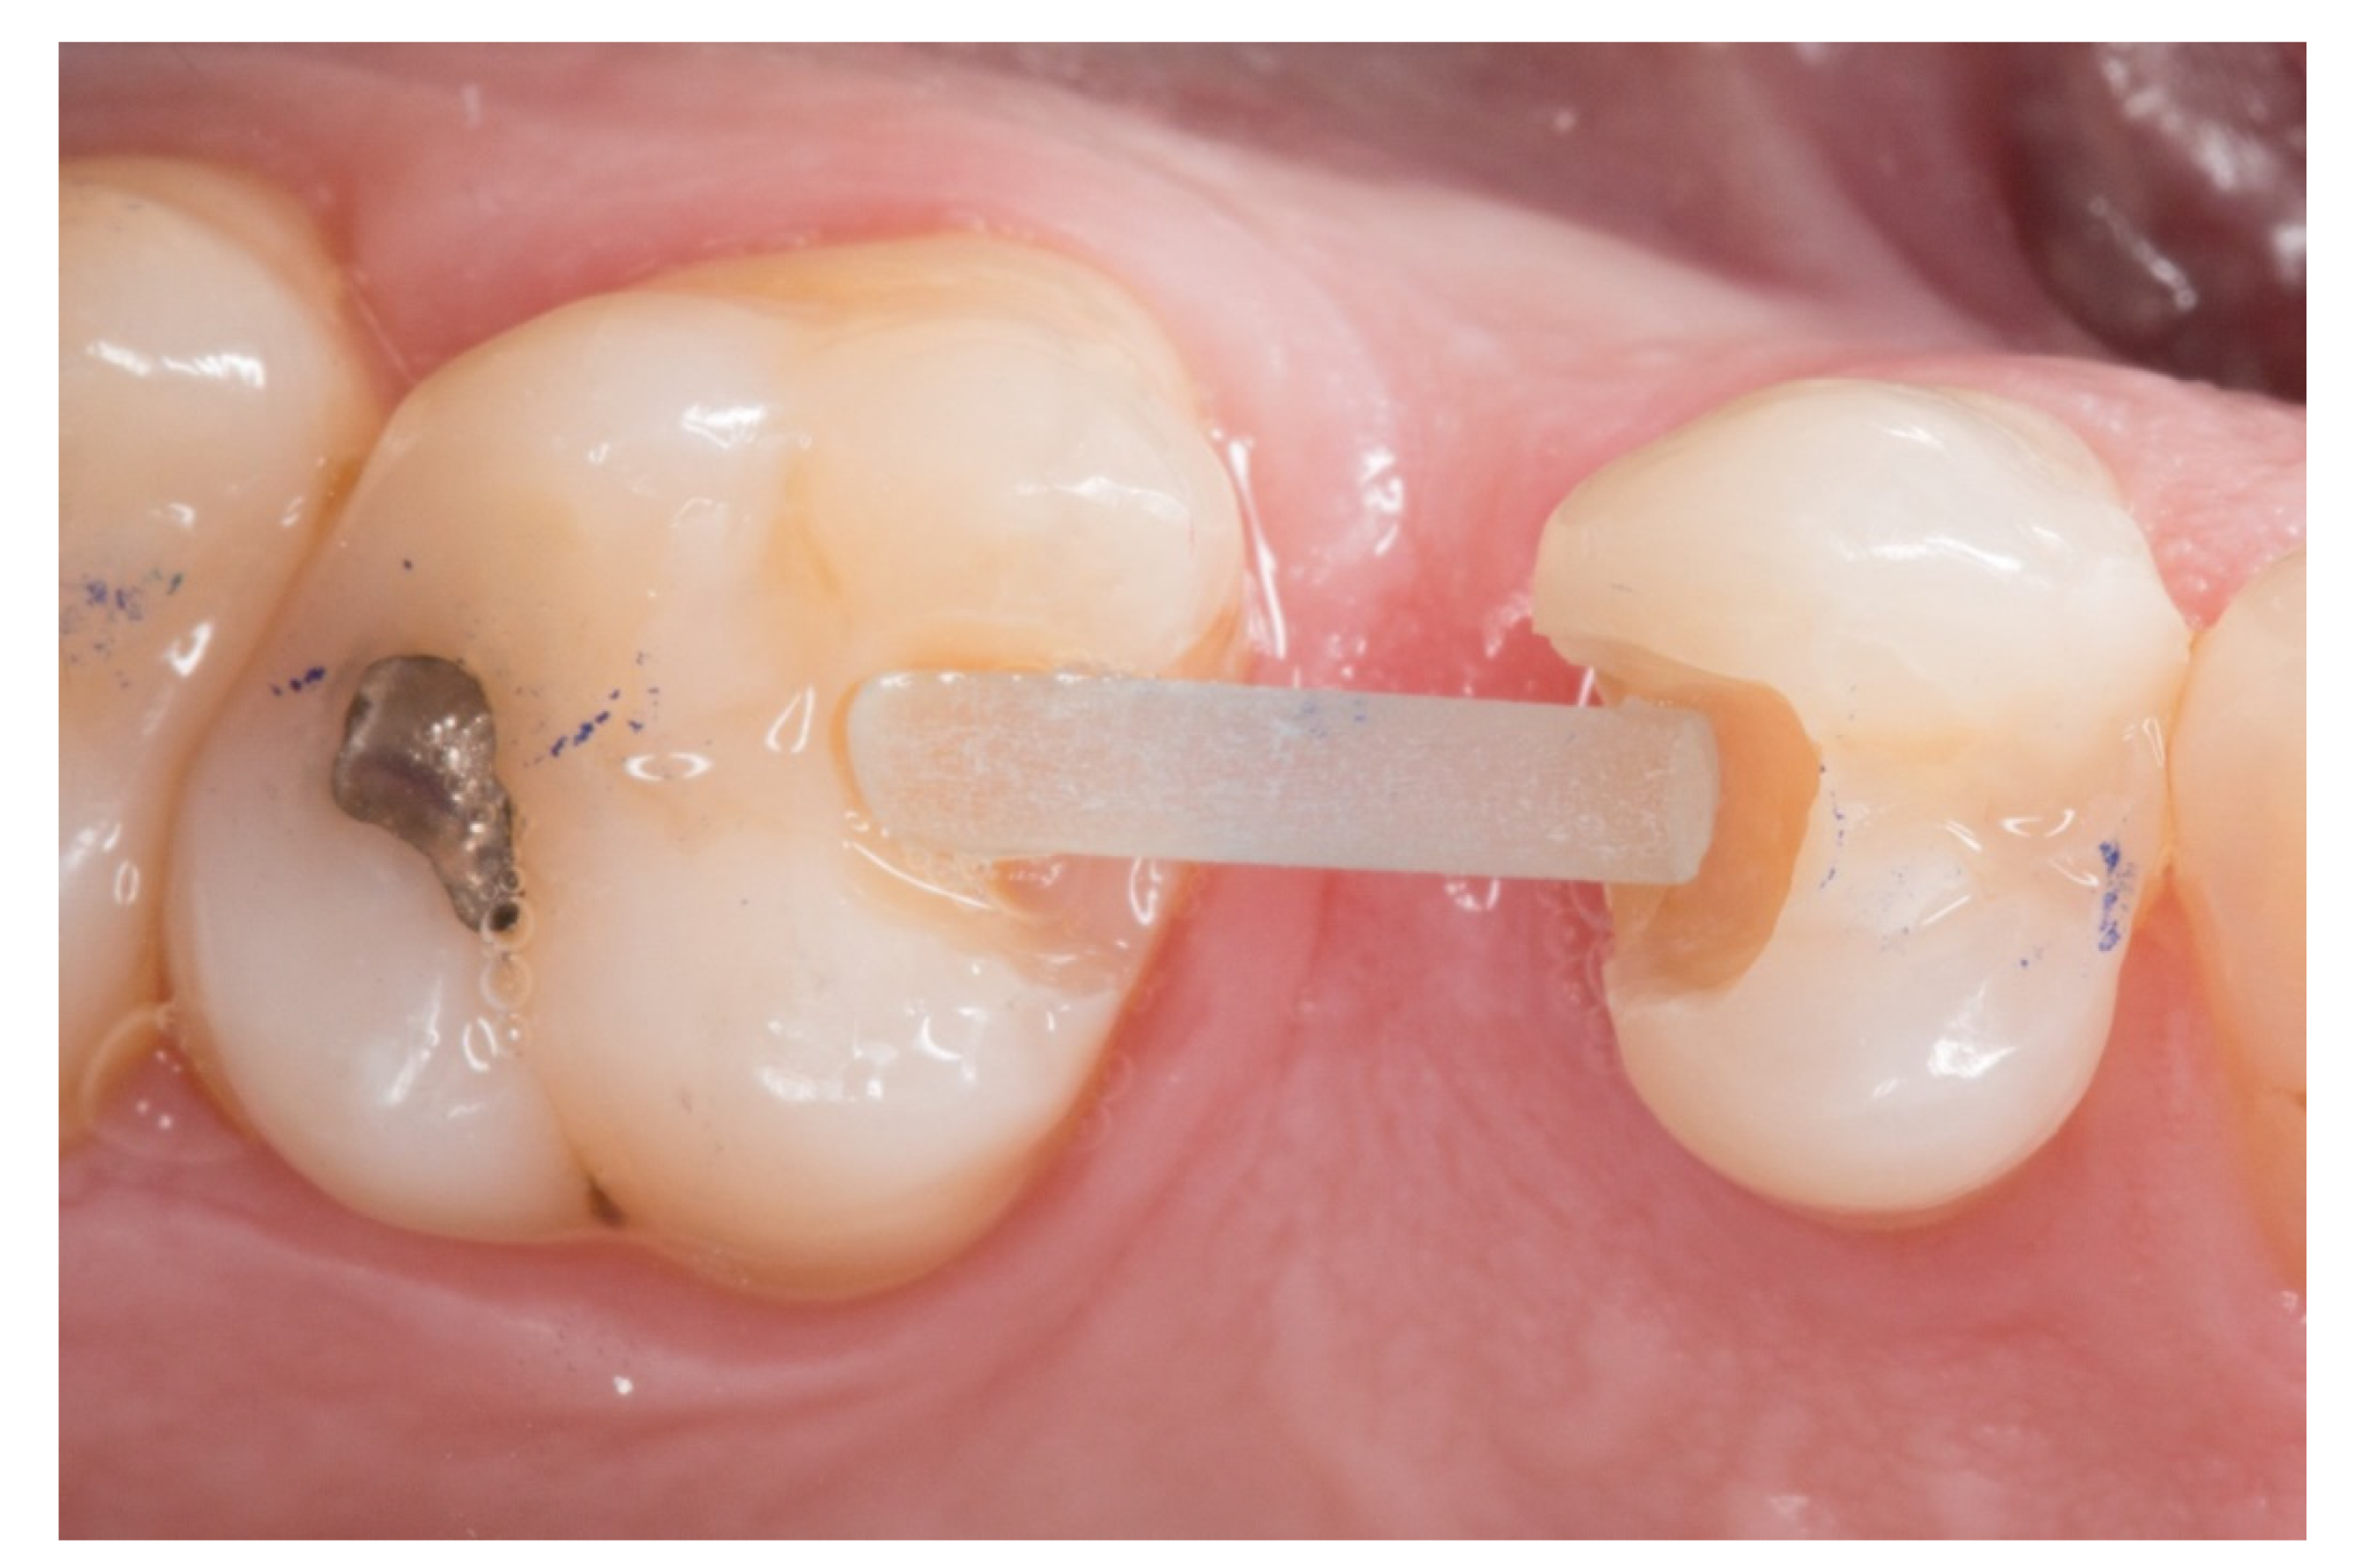

Figure 2.

The proximal faces of the adjacent teeth delimiting the edentulous space carved up to the level of the ideal point of contact (inlay cavities).

2. The proximal faces of the adjacent teeth delimiting the edentulous space were carved up to the level of the ideal point of contact (inlay cavities), to position the future horizontal structure of the fiberglass bridge (Figure 2).